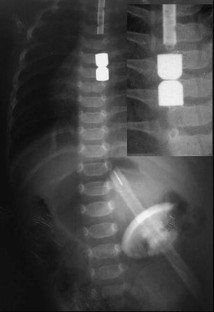

Between September 2001 and March 2004, five children were selected for treatment. Two of the children had esophageal atresia without fistula (type A) and three had atresia with fistula converted to type A surgically; however, surgeons failed to achieve an anastomosis because of the width of the gap. Neodymium-iron-boron magnets were used. Daily chest radiographs were taken until union of the magnets was observed. They were then replaced with an orogastric tube.

Anastomosis was achieved in all patients in an average of 4.8 days. One patient, with signs of early sepsis, was successfully treated with antibiotics. In four of the five patients, esophageal stenosis developed. At the time of this report, two patients were free of treatment and on an oral diet (after 26 months), two patients required periodic balloon dilatation, and one patient had recently undergone surgery due to recurrent esophageal stenosis not amenable to balloon dilatation.

Fig. 1